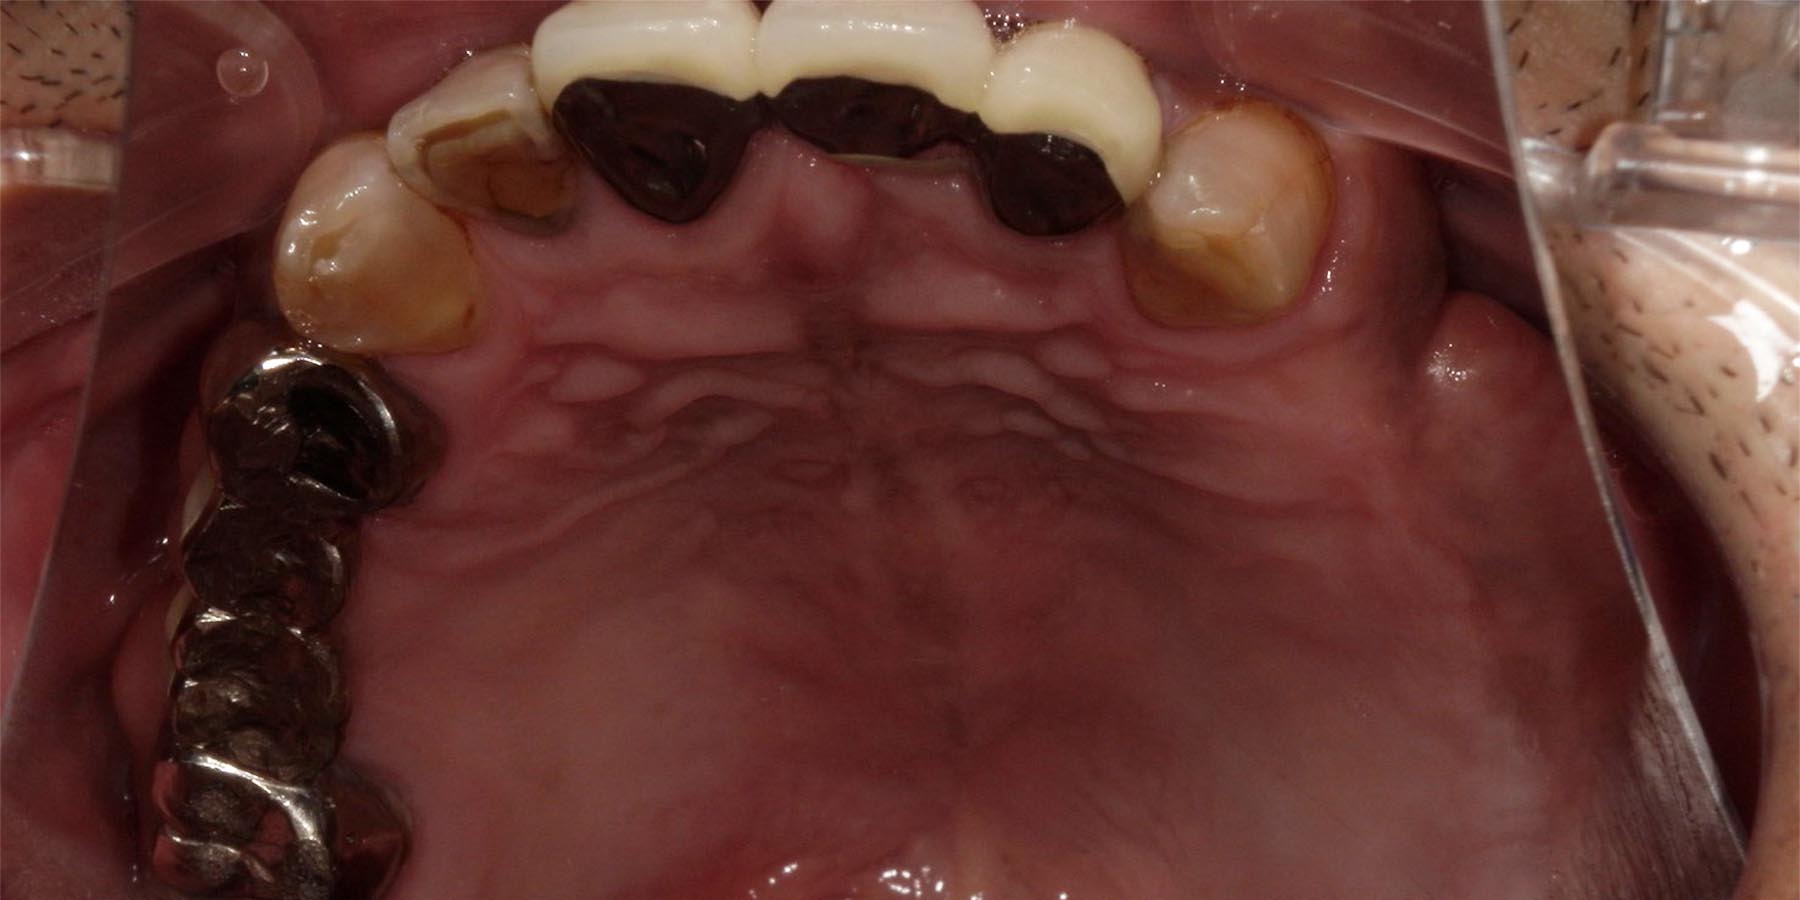

治療前